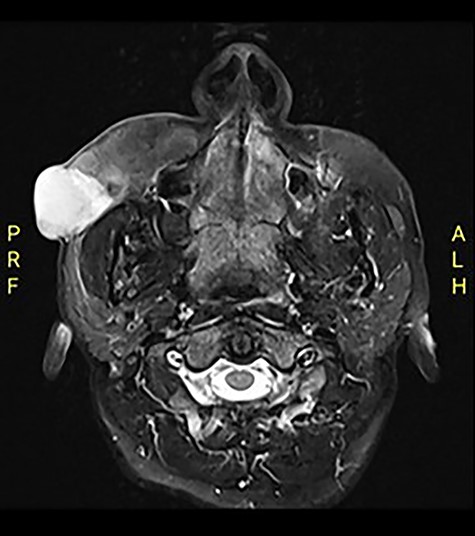

Computed tomography (CT) revealed an exophytic skin lesion on the right cheek reaching the buccal space with maximum transverse, anteroposterior and craniocaudal dimensions of 31, 28, 30 mm, respectively. No bone invasion was noted. Magnetic resonance imaging (MRI) indicated that the mass extended to the anterior surface of the masseter muscle, with parotid duct medialization due to mass effect (Fig. 1). The referred histopathology slide of the incisional biopsy was reviewed, and a diagnosis of DFSP was confirmed.